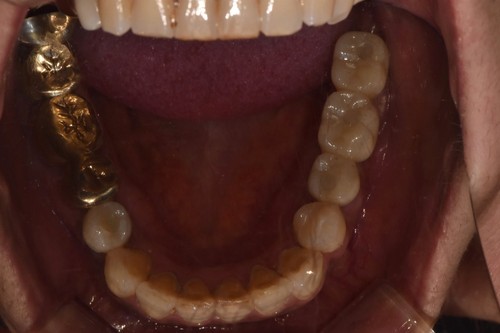

임플란트를 식립한 후에는 통상적으로는 3개월 후에 임플란트 보철물이 들어가는데 환자분의 사정으로 치과 내원을 못 하셔서 약 5개월 후에 오셨는데 왼쪽 아래 치아의 뿌리 부위의 충치가 발견되어서 아래 치아는 발치하면서 식립하는 즉시식립을 해 드렸습니다.

보통 하악에 임플란트 식립하면 2개월 이내에 치아가 들어가는데 마찬가지로 환자분 사정으로 못 오시다가 6개월이 지나서야 위,아래 임플란트 머리가 들어가고 마무리 할수 있었습니다.